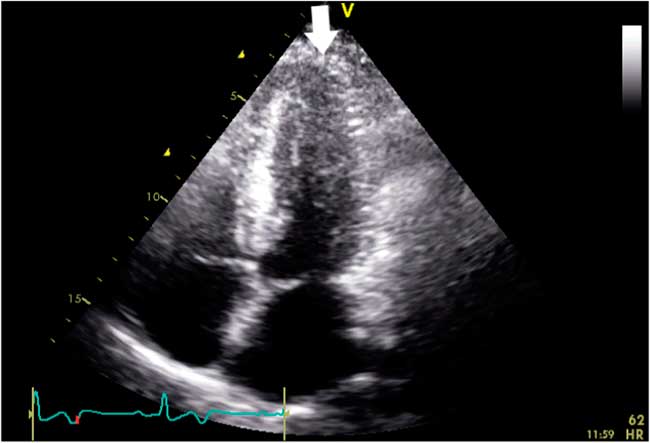

Four months later, the patient was seen at an outpatient follow-up by his cardiologist and was well. Oral metoprolol was continued. Cardiac magnetic resonance imaging (MRI) was suboptimal but appeared to show an “ace-of-spades” configuration (Figure 4). A repeat transthoracic echocardiogram confirmed ApHCM with a progressive increase in wall thickness toward the apex with a wall thickness greater than 15 mm. A 24-hour Holter monitor showed predominantly a sinus rhythm with infrequent asymptomatic premature atrial contractions and no ventricular ectopy.

Figure 4 Cardiac magnetic resonance imaging demonstrating progressive thickening of myocardium toward the left ventricular apex (white arrow)